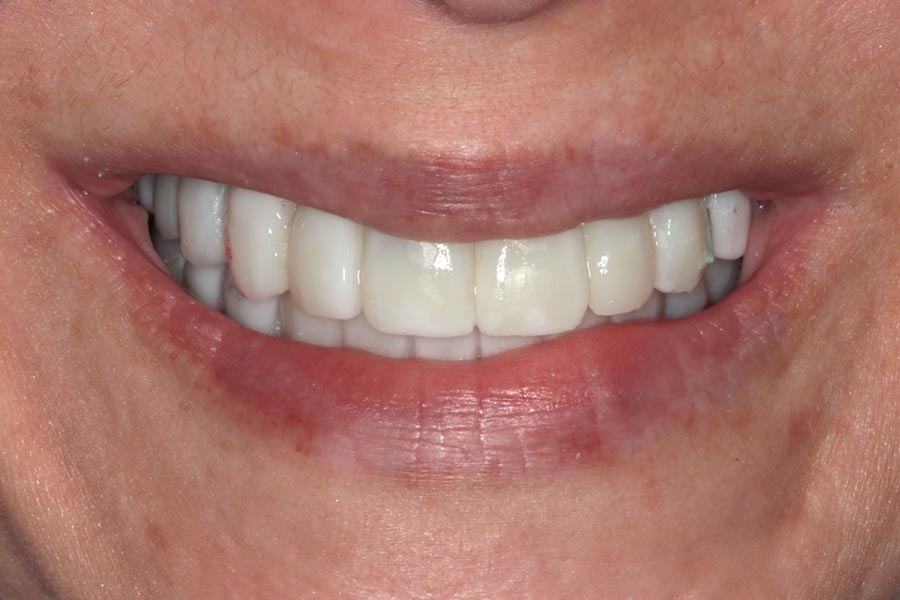

The patient travelled from another state for treatment so we only saw her again 3 months after surgery, when she was ready to start on the final prosthetic phase of treatment.

We use the provisionals at this stage as a starting point for designing definitive restorations. We assess them critically and discuss improvements that we would like to see. Tissues have also stabilized at this stage so the final restorations will be designed to compensate for any resorption that has taken place.

Prototypes are design and fabricated in wax so we can dial in the esthetics that we are looking for. In this particular case, a little pink was designed on the lower to compensate for tissue resorption while keeping tooth length proportional and balanced.